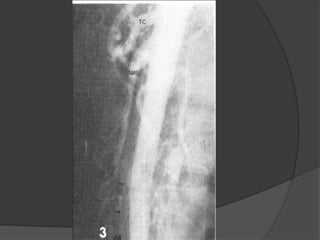

CAYADO AÓRTICO

Circuito Vertebro-basilar

Arterias Vertebrales